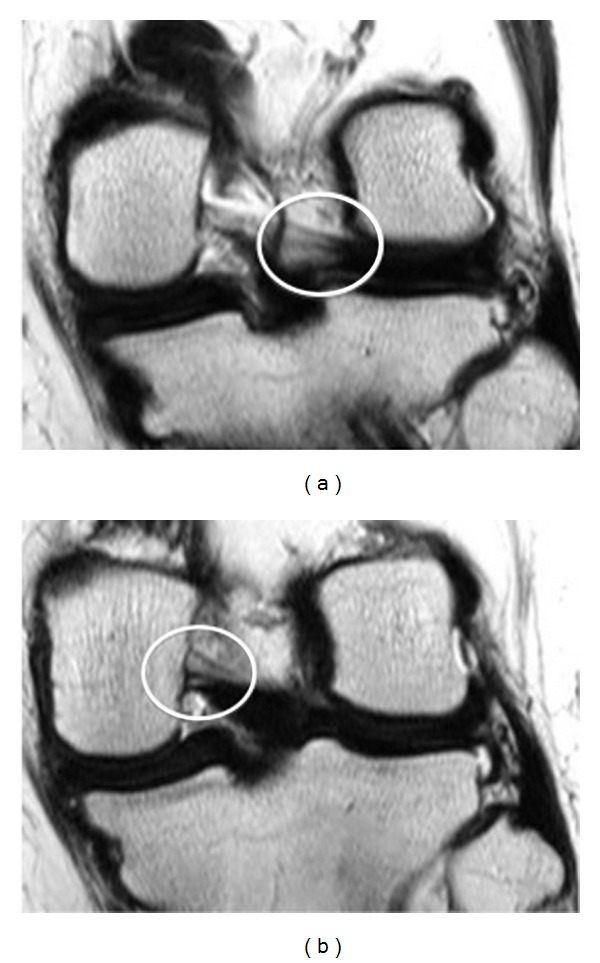

虽然半月板股骨韧带是不同的解剖单位,但从解剖学和放射学的角度来看,其解剖和功能存在争议。回顾性研究了500例膝关节MR检查,以证明其发病率和性别、年龄分布的变化,以及磁共振成像半月板股骨韧带的解剖结构。患者大多是男性,有312人,相比之下,女性患者较少,有188人。纳入这项研究的患者平均年龄为46岁。其中一半以上的人年龄在20到40岁之间;20 ~ 30岁133例,31 ~ 40岁101例,共234例。

Although meniscofemoral ligaments are distinct anatomic units, their anatomy and function are controversial from an anatomic and radiologic point of view. Five hundred knee MR examinations were retrospectively studied in an effort to demonstrate the incidence and variations regarding sex and age distribution, as well as the anatomy of the meniscofemoral ligament at magnetic resonance imaging. Patients were mostly men, three hundred and twelve, in contrast with women who were fewer, one hundred eighty-eight patients. The mean age of the patients who were included in this study was 46 years. More than half of them were between 20 and 40 years old; one hundred thirty-three patients among 20 to 30 years old and one hundred and one patients among 31 and 40 years old, in total two hundred thirty-four patients.